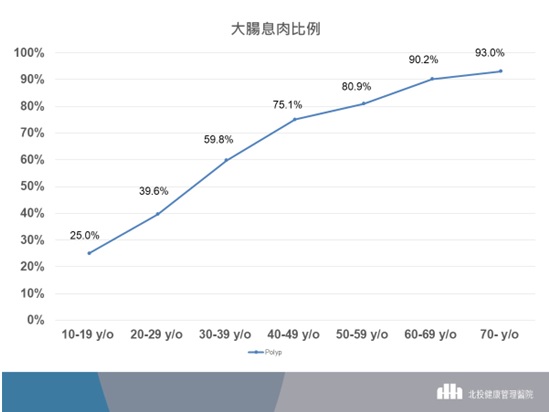

黃洸偉主任醫師也表示,北投健康管理醫院內視鏡中心統計發現,針對無症狀的健康或亞健康的來檢者民眾,整體有大腸息肉的比例可高達75.8%(圖一),30-39歲的族群有大腸息肉的比例為59.8%,而40-49歲的族群有大腸息肉的比例更高達75.1%。然而並不是所有的大腸息肉都會癌變,「腺瘤型息肉」一般被認知為會逐漸長大並轉變為大腸癌,而風險真正高的是「進行性腺瘤(advanced adenoma)」,指的是有較高風險轉變為癌症的腺瘤,也就是1公分以上、病理化驗後有絨毛成分(villous component)、高度細胞異型變化(high-grade dysplasia)的腺瘤。

▲(圖一)以歷年統計資料來看,30-39歲的族群有大腸息肉的比例為59.8%,而40-49歲的族群有大腸息肉的比例更高達75.1%。